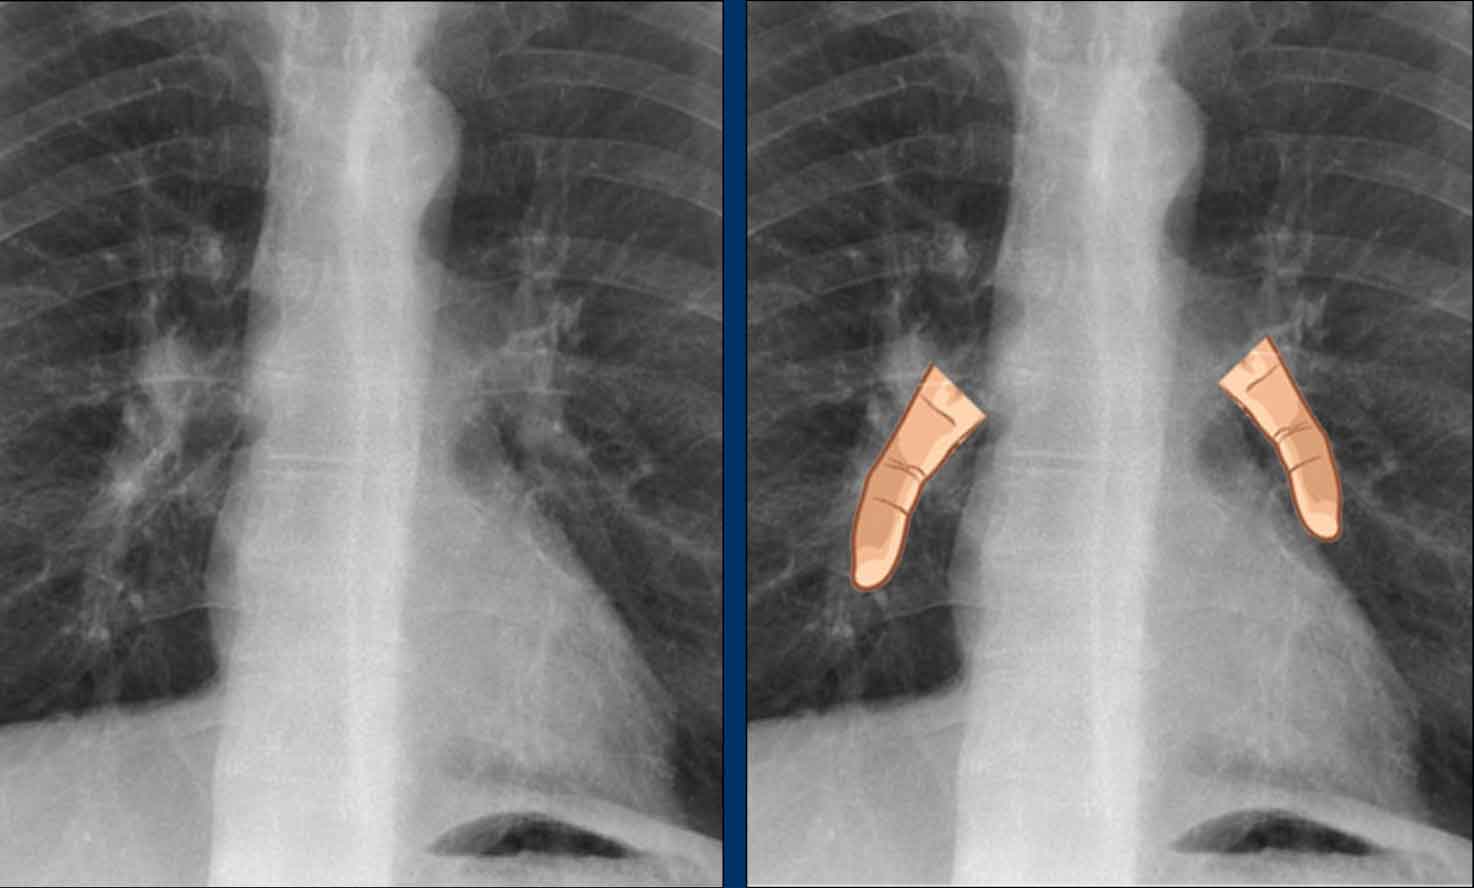

Hidden area (5): Mass Behind the First Rib

In some patients, an accessory joint at the anterior aspect of the first rib may simulate a mass, as we learned earlier.

However this area is also a "hidden zone", where true lesions can be masked.

• In this case, a small lung carcinoma was obscured by the left first rib on the PA view.

• On the lateral film, the lesion is visible in the retrosternal space.

Continue with the PET-CT...

Subsequent PET-CT imaging confirmed a hypermetabolic tumor (arrow), with metastases to the bone and liver.

• Diagnosis was confirmed via biopsy of an osteolytic metastasis in the iliac bone.